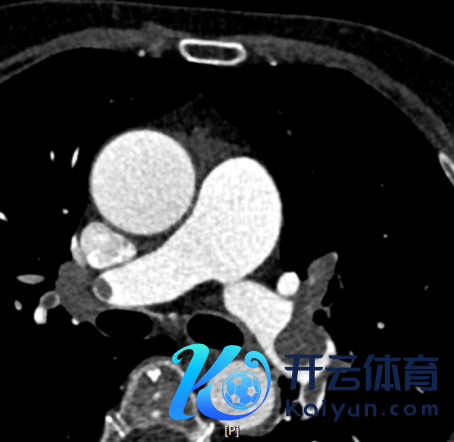

强化CT扫描刚完结,CT见“双肺动脉、双侧各叶段动脉内见多发条片状低密度充盈缺损,冠状动脉前降支局限性非钙化斑块,管腔轻微褊狭”(图3-5)。

图4.CTPA成果